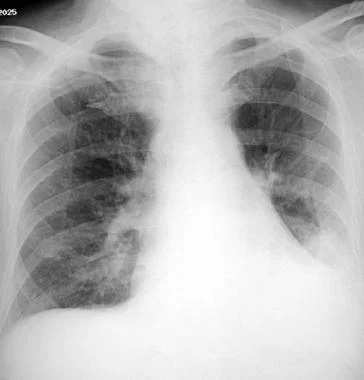

吸入性肺炎的影像学取决于吸入发生时患者的位置。因右主支气管直径更大且更陡直 ,所以右下肺是最常见的浸润部位。站立时发生抽吸的患者可出现双下肺浸润。左侧卧位的患者更可能出现左侧浸润(见图1)。右上叶更可能是俯卧位吸气的酗酒者。

图1 患者过量使用苯二氮卓类药物,左肺显示吸入性肺炎。吸入发生时,患者可能位于左侧